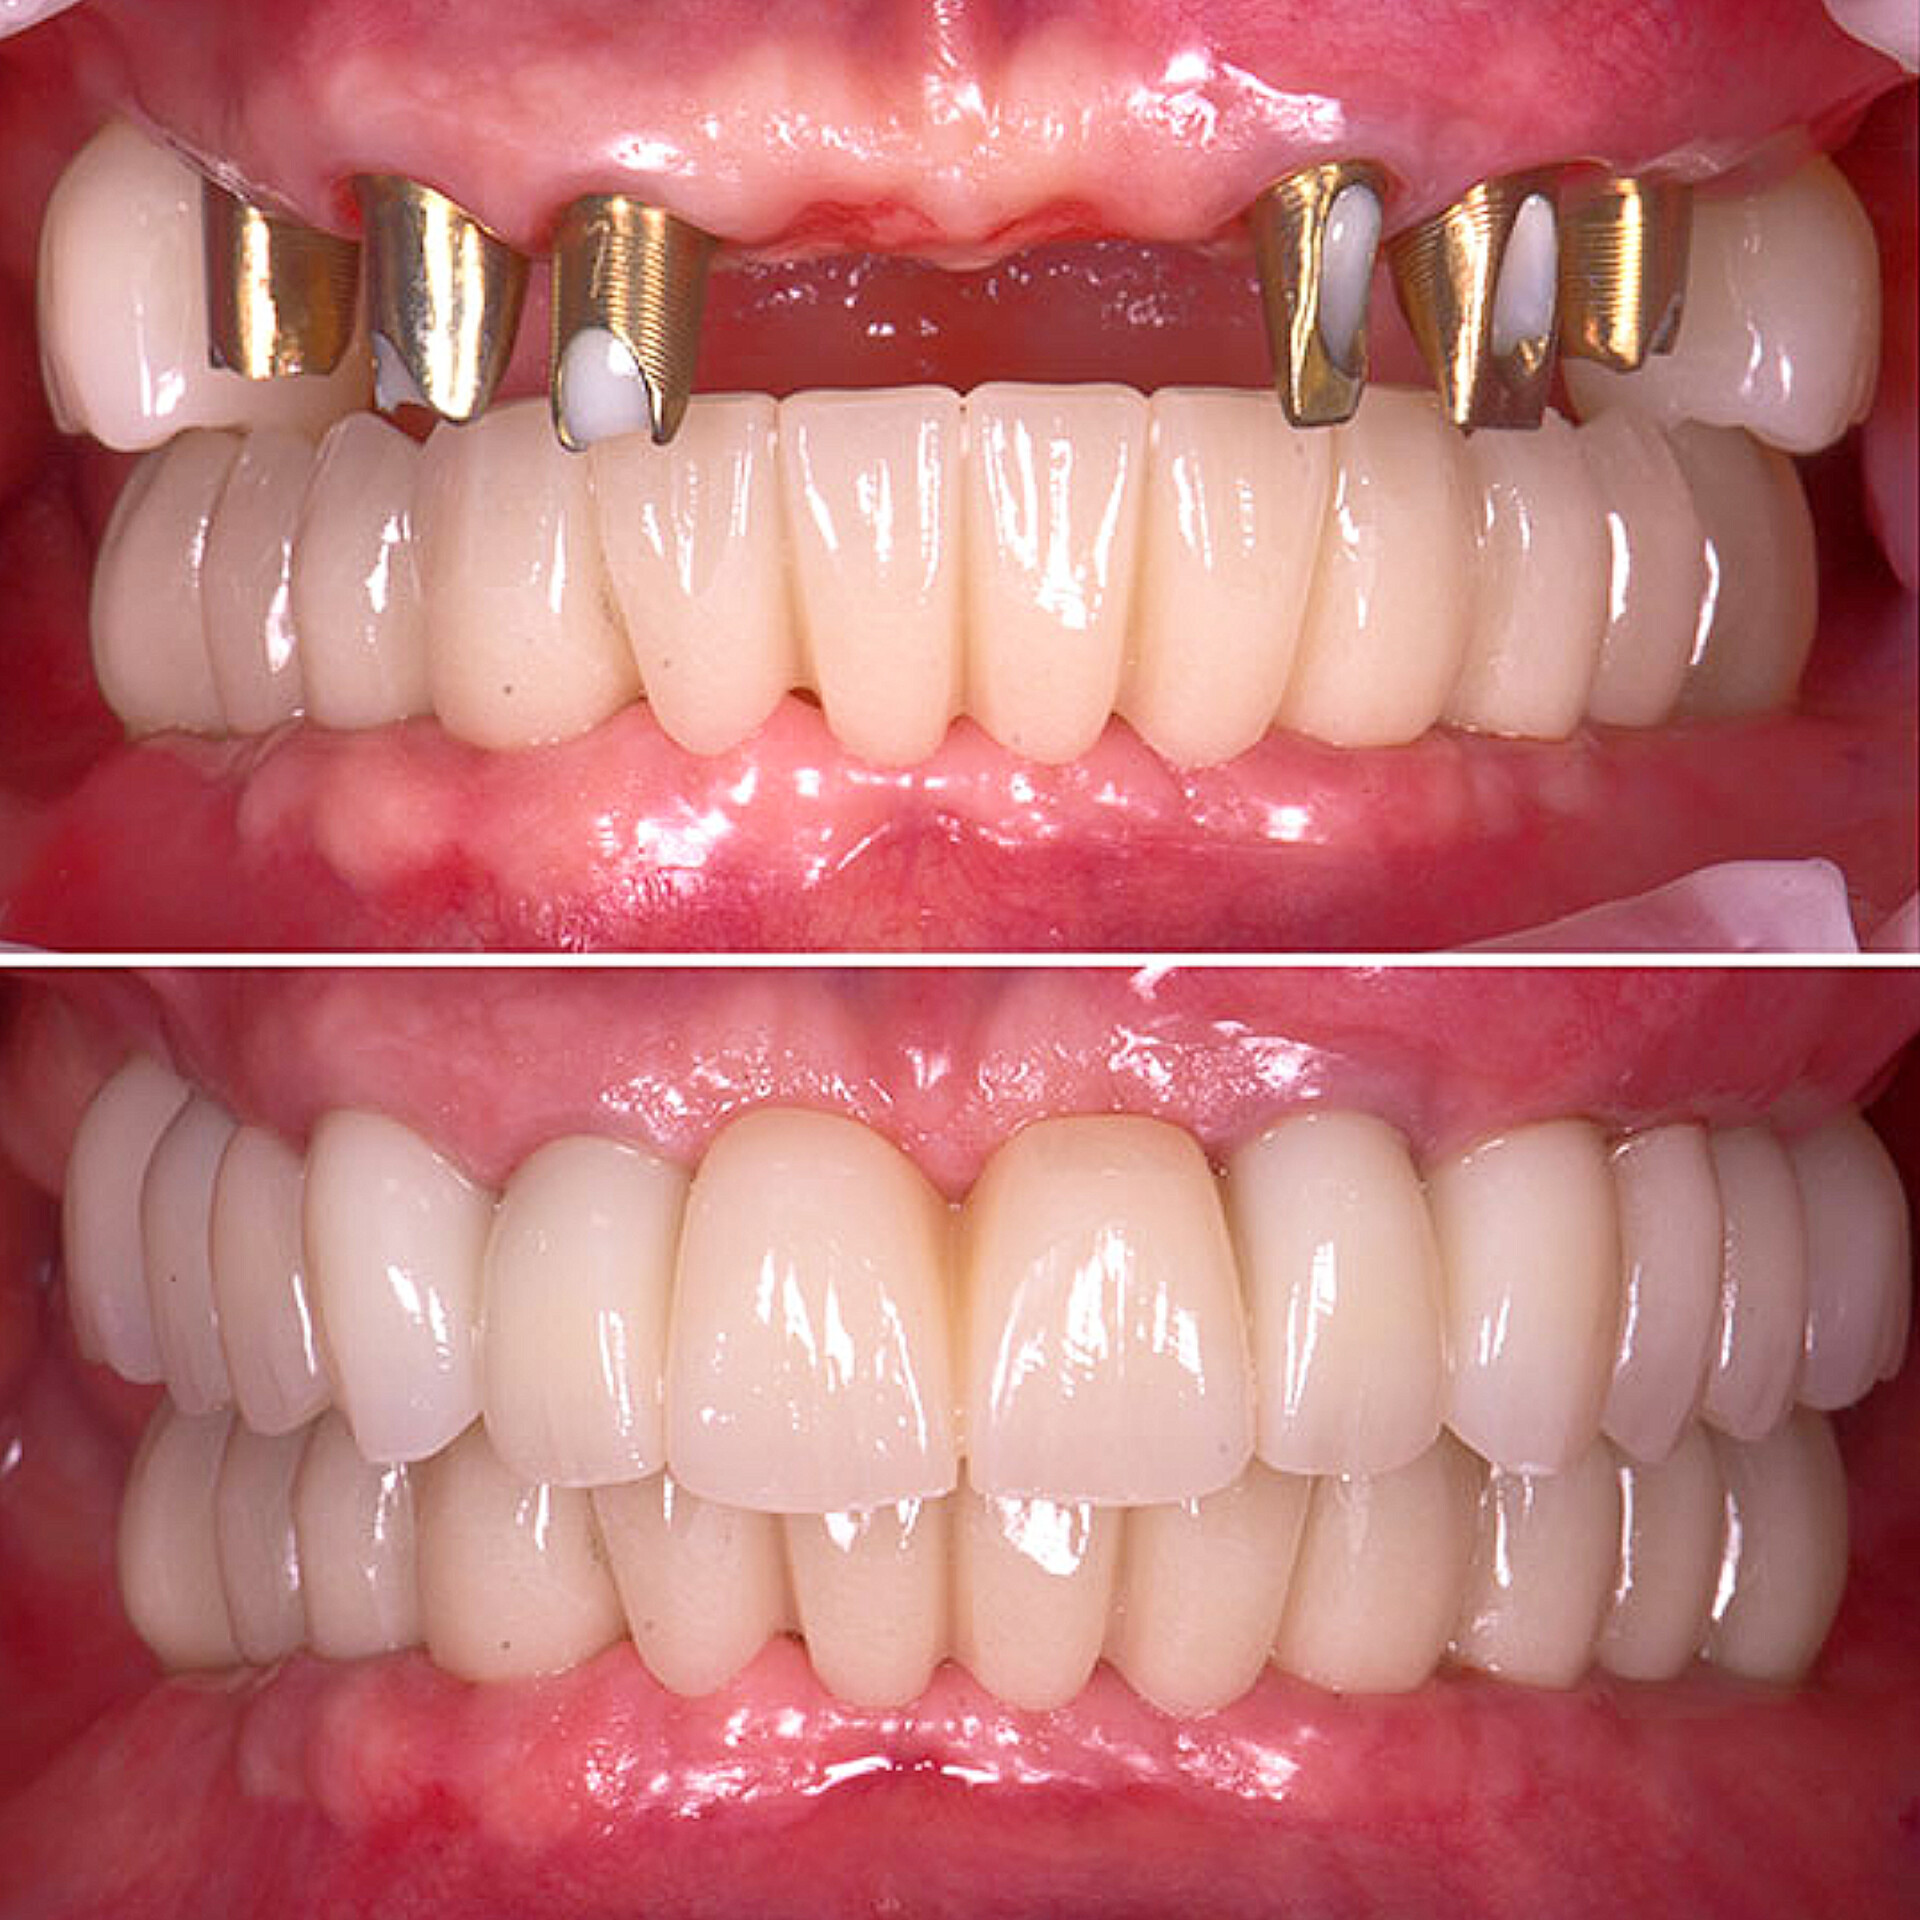

۶. پروتزهای دندانی

ساخت انواع پروتزهای ثابت (روکش و بریج) و متحرک (دندان مصنوعی) با استفاده از مواد باکیفیت و در لابراتوار مجهز انجام میشود.